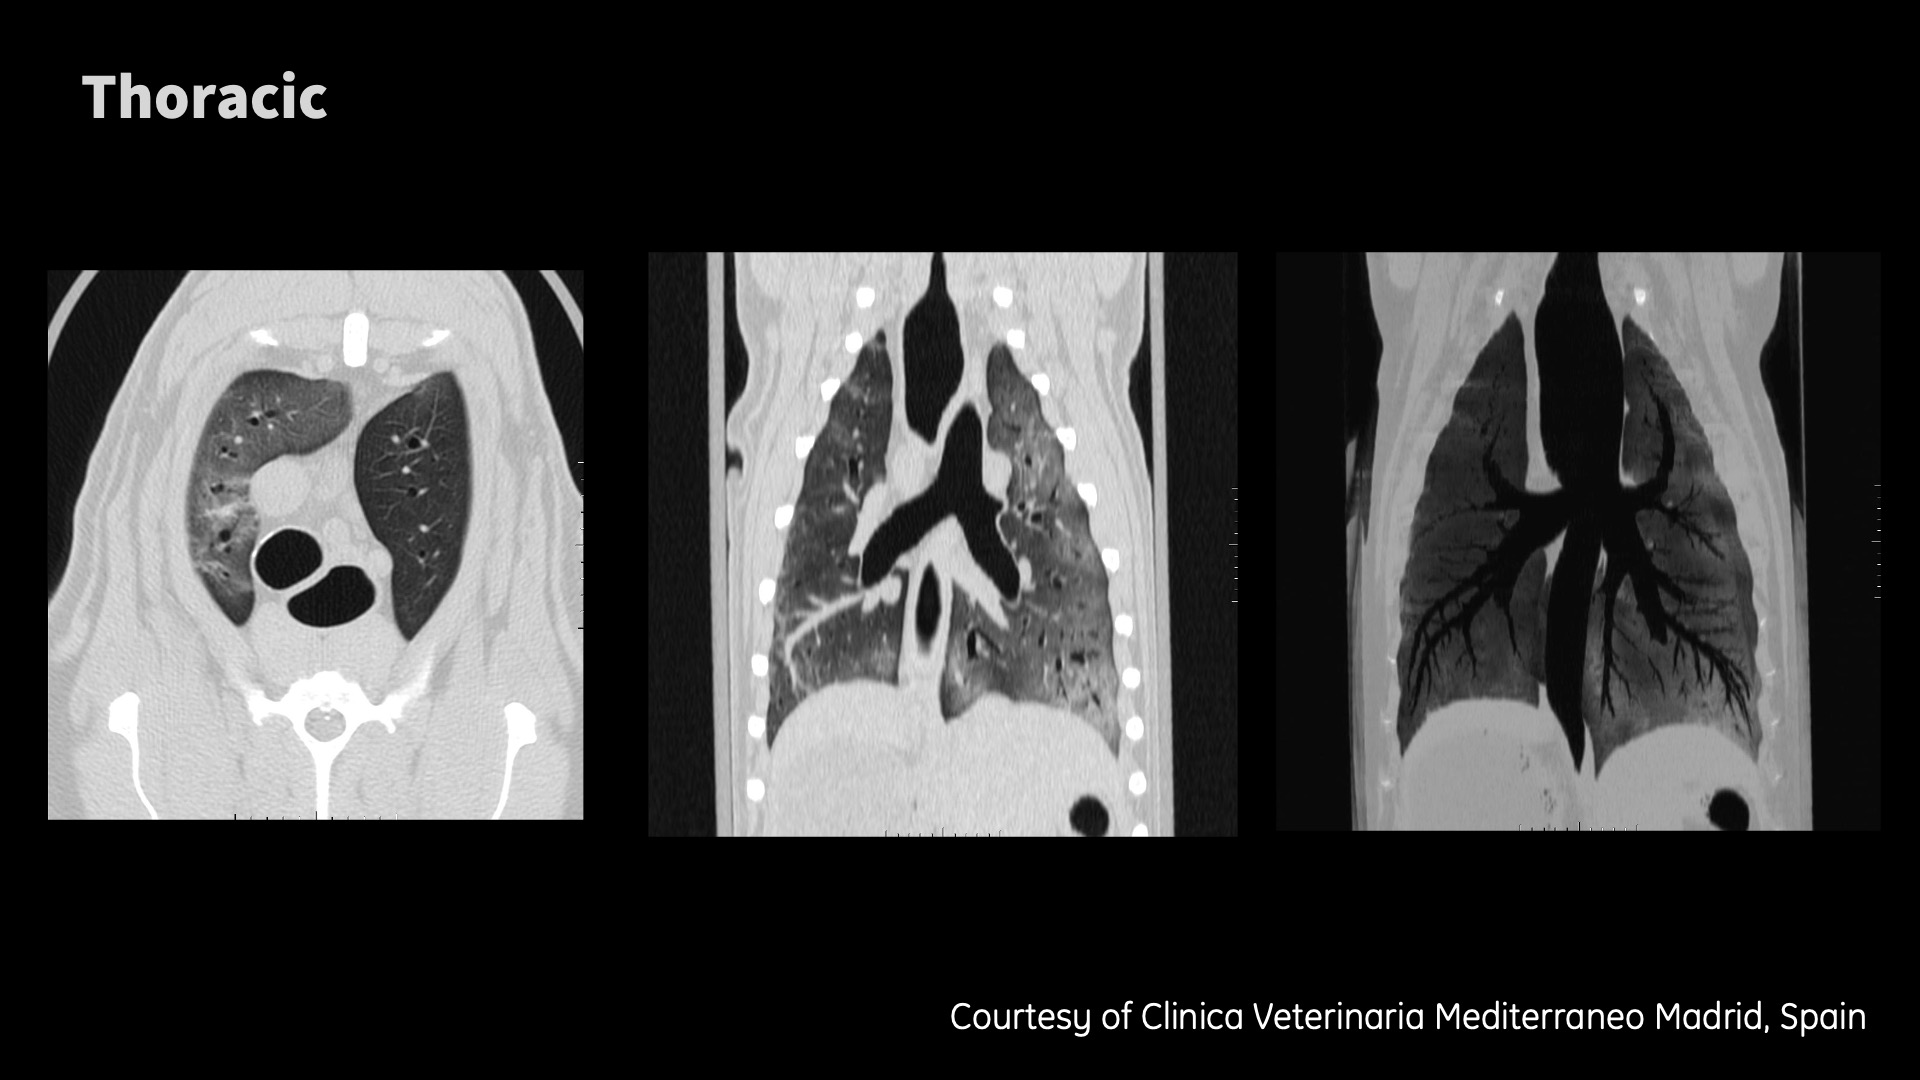

Clinical images

Don’t need to be an eagle to see the details